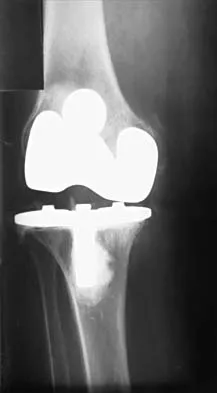

Figure 3 shows the AP radiograph of a patient with diabetes mellitus who has knee pain. A semiconstrained knee prosthesis was used in this patient to prevent which of the following complications?

Explanation

The radiographic appearance of the joint is highly suspicious for neuropathic joint (Charcot's joint). Evidence of bone loss on both the tibial and the femoral sides may necessitate the use of metal and/or bone augments. Patients with a neuropathic joint often have excellent range of motion, and postoperative stiffness is not a problem. The main problem with these patients is instability that occurs secondary to ligamentous laxity. Use of a semiconstrained prosthesis prevents the latter complication. Parvizi J, Marrs J, Morrey BF: Total knee arthroplasty for neuropathic (Charcot) joints. Clin Orthop 2003;416:145-150.